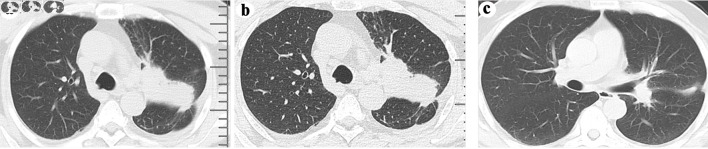

肺癌的侵袭性常常伴随着骨转移的高发病率;然而,与其他恶性肿瘤相比,肺癌引起的股骨近端转移并不常见。在本报告中,我们介绍了一名 53 岁亚洲男性的病例,他因左大腿和背部疼痛而就诊。磁共振成像显示左大腿处有严重的骨质破坏,邻近的软组织肿块也受累,成像结果与骨肉瘤相似。随后的骨活检确诊为表皮生长因子受体(EGFR)突变的肺腺癌并发骨转移。患者在服用奥希替尼后获得了生存,并接受了股骨转移手术,而没有接受肺癌姑息手术。因此,在怀疑患有骨肉瘤的患者中,应将表皮生长因子受体(EGFR)突变的肺腺癌引起的股骨近端转移作为鉴别诊断。本文介绍了表皮生长因子受体(EGFR)突变肺腺癌股骨近端转移的影像学检查结果,并讨论了其治疗方法。

The aggressive nature of lung cancer is frequently accompanied by a high incidence of bone metastasis; however, proximal femoral metastasis from lung cancer is comparatively uncommon when compared to other malignancies. In this report, we present the case of a 53-year-old Asian male who presented with pain in the left thigh and back. Magnetic resonance imaging revealed severe bone destruction with involvement of adjacent soft tissue mass at the left thigh, exhibiting imaging findings that mimic osteosarcoma. Subsequent bone biopsy confirmed the diagnosis of epidermal growth factor receptor (EGFR)-mutated lung adenocarcinoma with bone metastasis. The patient achieved survival following administration of osimertinib and underwent surgery for femoral metastases without palliative surgery for lung cancer. Therefore, proximal femoral metastasis from EGFR-mutated lung adenocarcinoma should be considered as a differential diagnosis in patients suspected to have osteosarcoma. The imaging findings of proximal femoral metastasis from EGFR-mutated lung adenocarcinoma were presented, and their therapeutic management was discussed.